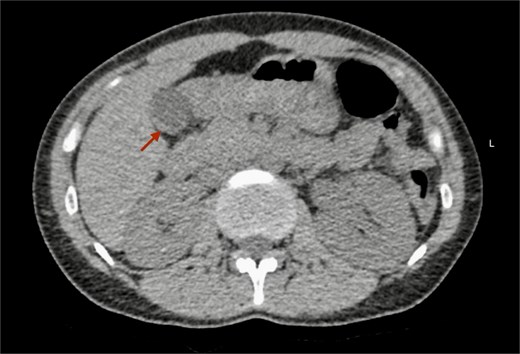

Imaging findings: A non-contrast computed tomography (CT) scan of the abdomen revealed a mild left hydroureteronephrosis caused by a distal obstructive ureteric stone. Incidentally, the scan showed a focal thickening of the gallbladder fundus wall (Fig. 1). Correlation with abdominal ultrasound identified a well-defined 7 mm cystic lesion within the gallbladder wall (Fig. 2). The liver, spleen, and other abdominal organs appeared normal on CT.

Non-contrast CT scan of the abdomen. The axial plane shows focal thickening of the gallbladder wall (arrow).